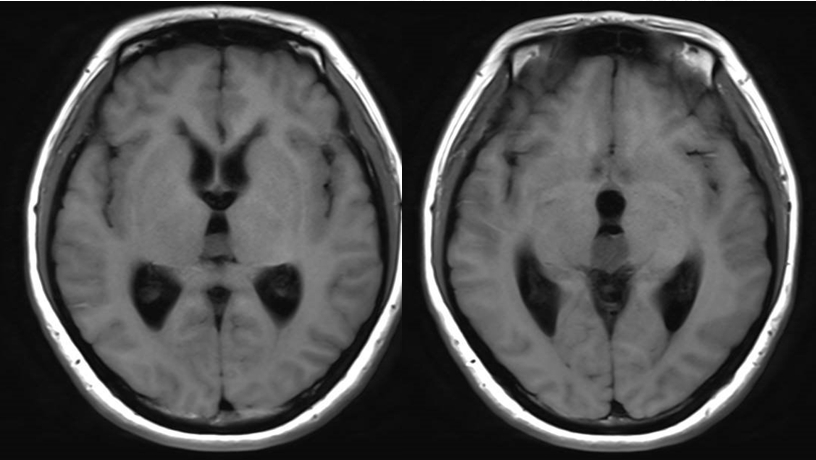

中年女性,因“头痛伴记忆力减退1月” 入院;

查体:神志清醒,反应迟钝,精神差,高级认知功能差,双下肢肌力IV级;

诊断:三脑室占位,梗阻性脑积水。

诊治过程:结合患者临床表现及影像学表现,初步诊断考虑为三脑室后部胶质瘤合并梗阻性脑积水可能性大,术前制定的手术方案为经胼胝体穹隆间入路三脑室后部肿瘤切除术+脑室镜辅助下三脑室底造瘘术,该手术方式既可切除肿瘤获取病理,同时可行三脑室底造瘘解决脑积水症状。术中采用冠状缝前额部弧形切口,术中沿纵裂牵开双侧大脑半球,探及胼胝体,沿中线切开胼胝体,分离双侧透明隔,暴露双侧穹隆,严格沿中线分离双侧穹隆,保护两侧穹隆的完整,避免引起术后的记忆力障碍,牵拉开双侧穹隆,进入中间帆,显露并分离双侧大脑内静脉继续向下,经脉络膜隔进入三脑室,完全显露肿瘤组织,肿瘤组织呈灰红色,血供极其丰富,与中脑黏连紧密,仔细分离,分块全切肿瘤,双侧大脑内静脉及中脑保护良好,中脑导水管通畅。肿瘤完全切除后,考虑到术后局部粘连、肿瘤复发等因素可能导致脑积水不缓解,置入脑室镜向前方探查,小心切开中间块,在双侧乳头体与漏斗隐窝之间,行三脑室底部造瘘并打开Liliequist膜及基底动脉旁蛛网膜,确认漏口通畅且与脚间池相通。患者术后恢复过程平稳,颅脑MRI提示肿瘤切除满意,脑积水缓解。术后病理结果示:中枢神经细胞瘤(2级)。术后予以放疗GTV 5400cGy、PTV 5040cGy,28f。现术后已3年,复查未见肿瘤复发,脑积水已完全缓解。